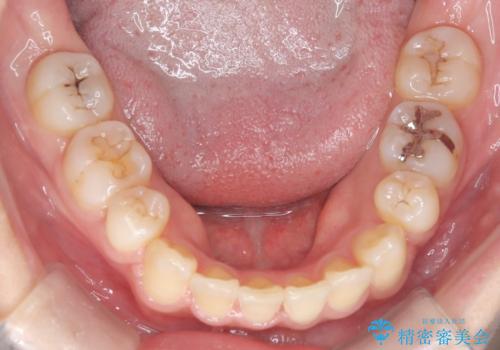

- 患者様は、歯並びのガタガタ(重度の叢生)を改善したいとのことで来院されました。診察すると、歯列のスペース不足が著しく、前歯が重なり合い、噛み合わせにも影響が出ている状態でした。歯をきれいに並べるためには抜歯によるスペース確保が不可欠と判断し、上下の小臼歯4本を抜歯したうえで、目立ちにくい審美ワイヤー矯正(白いワイヤーと透明ブラケット)を用いた治療計画を立てました。

抜歯によって歯を動かすためのスペースを確保。その後、審美ワイヤー矯正を用いて歯を1本ずつ適切な位置に誘導しながら、噛み合わせのバランスも整えていきました。時間はかかりましたが、ガタガタの歯並びがきれいに整い、機能的にも審美的にも満足のいく仕上がりとなりました。患者様からは「歯並びが劇的に改善し、見た目だけでなく噛みやすさも向上した」と喜びの声をいただきました。